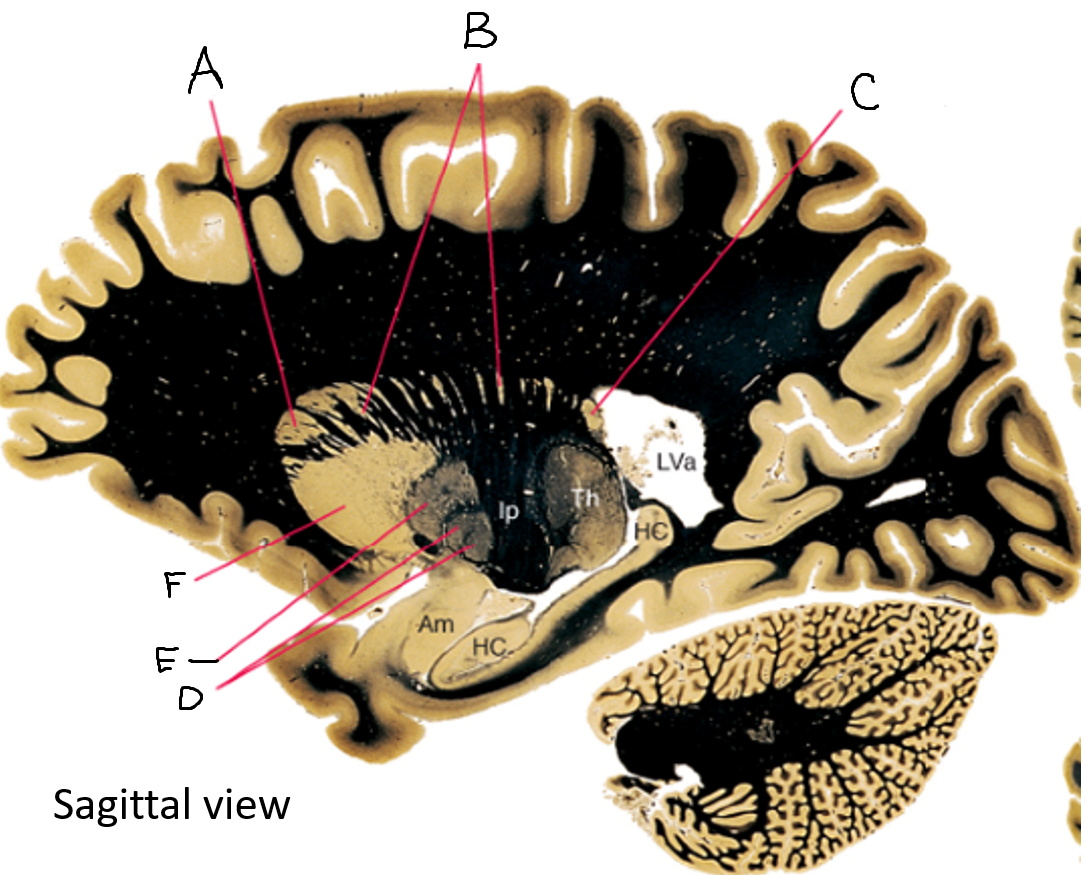

A

corpus callosum

B

lateral ventricle

C

internal capsule

D

third ventricle

E

tail of caudate nucleus

F

lateral ventricle

G

hippocampus

H

mammillary body

I

fornix

J

globus pallidus

K

putamen

L

caudate

M

thalamus

N